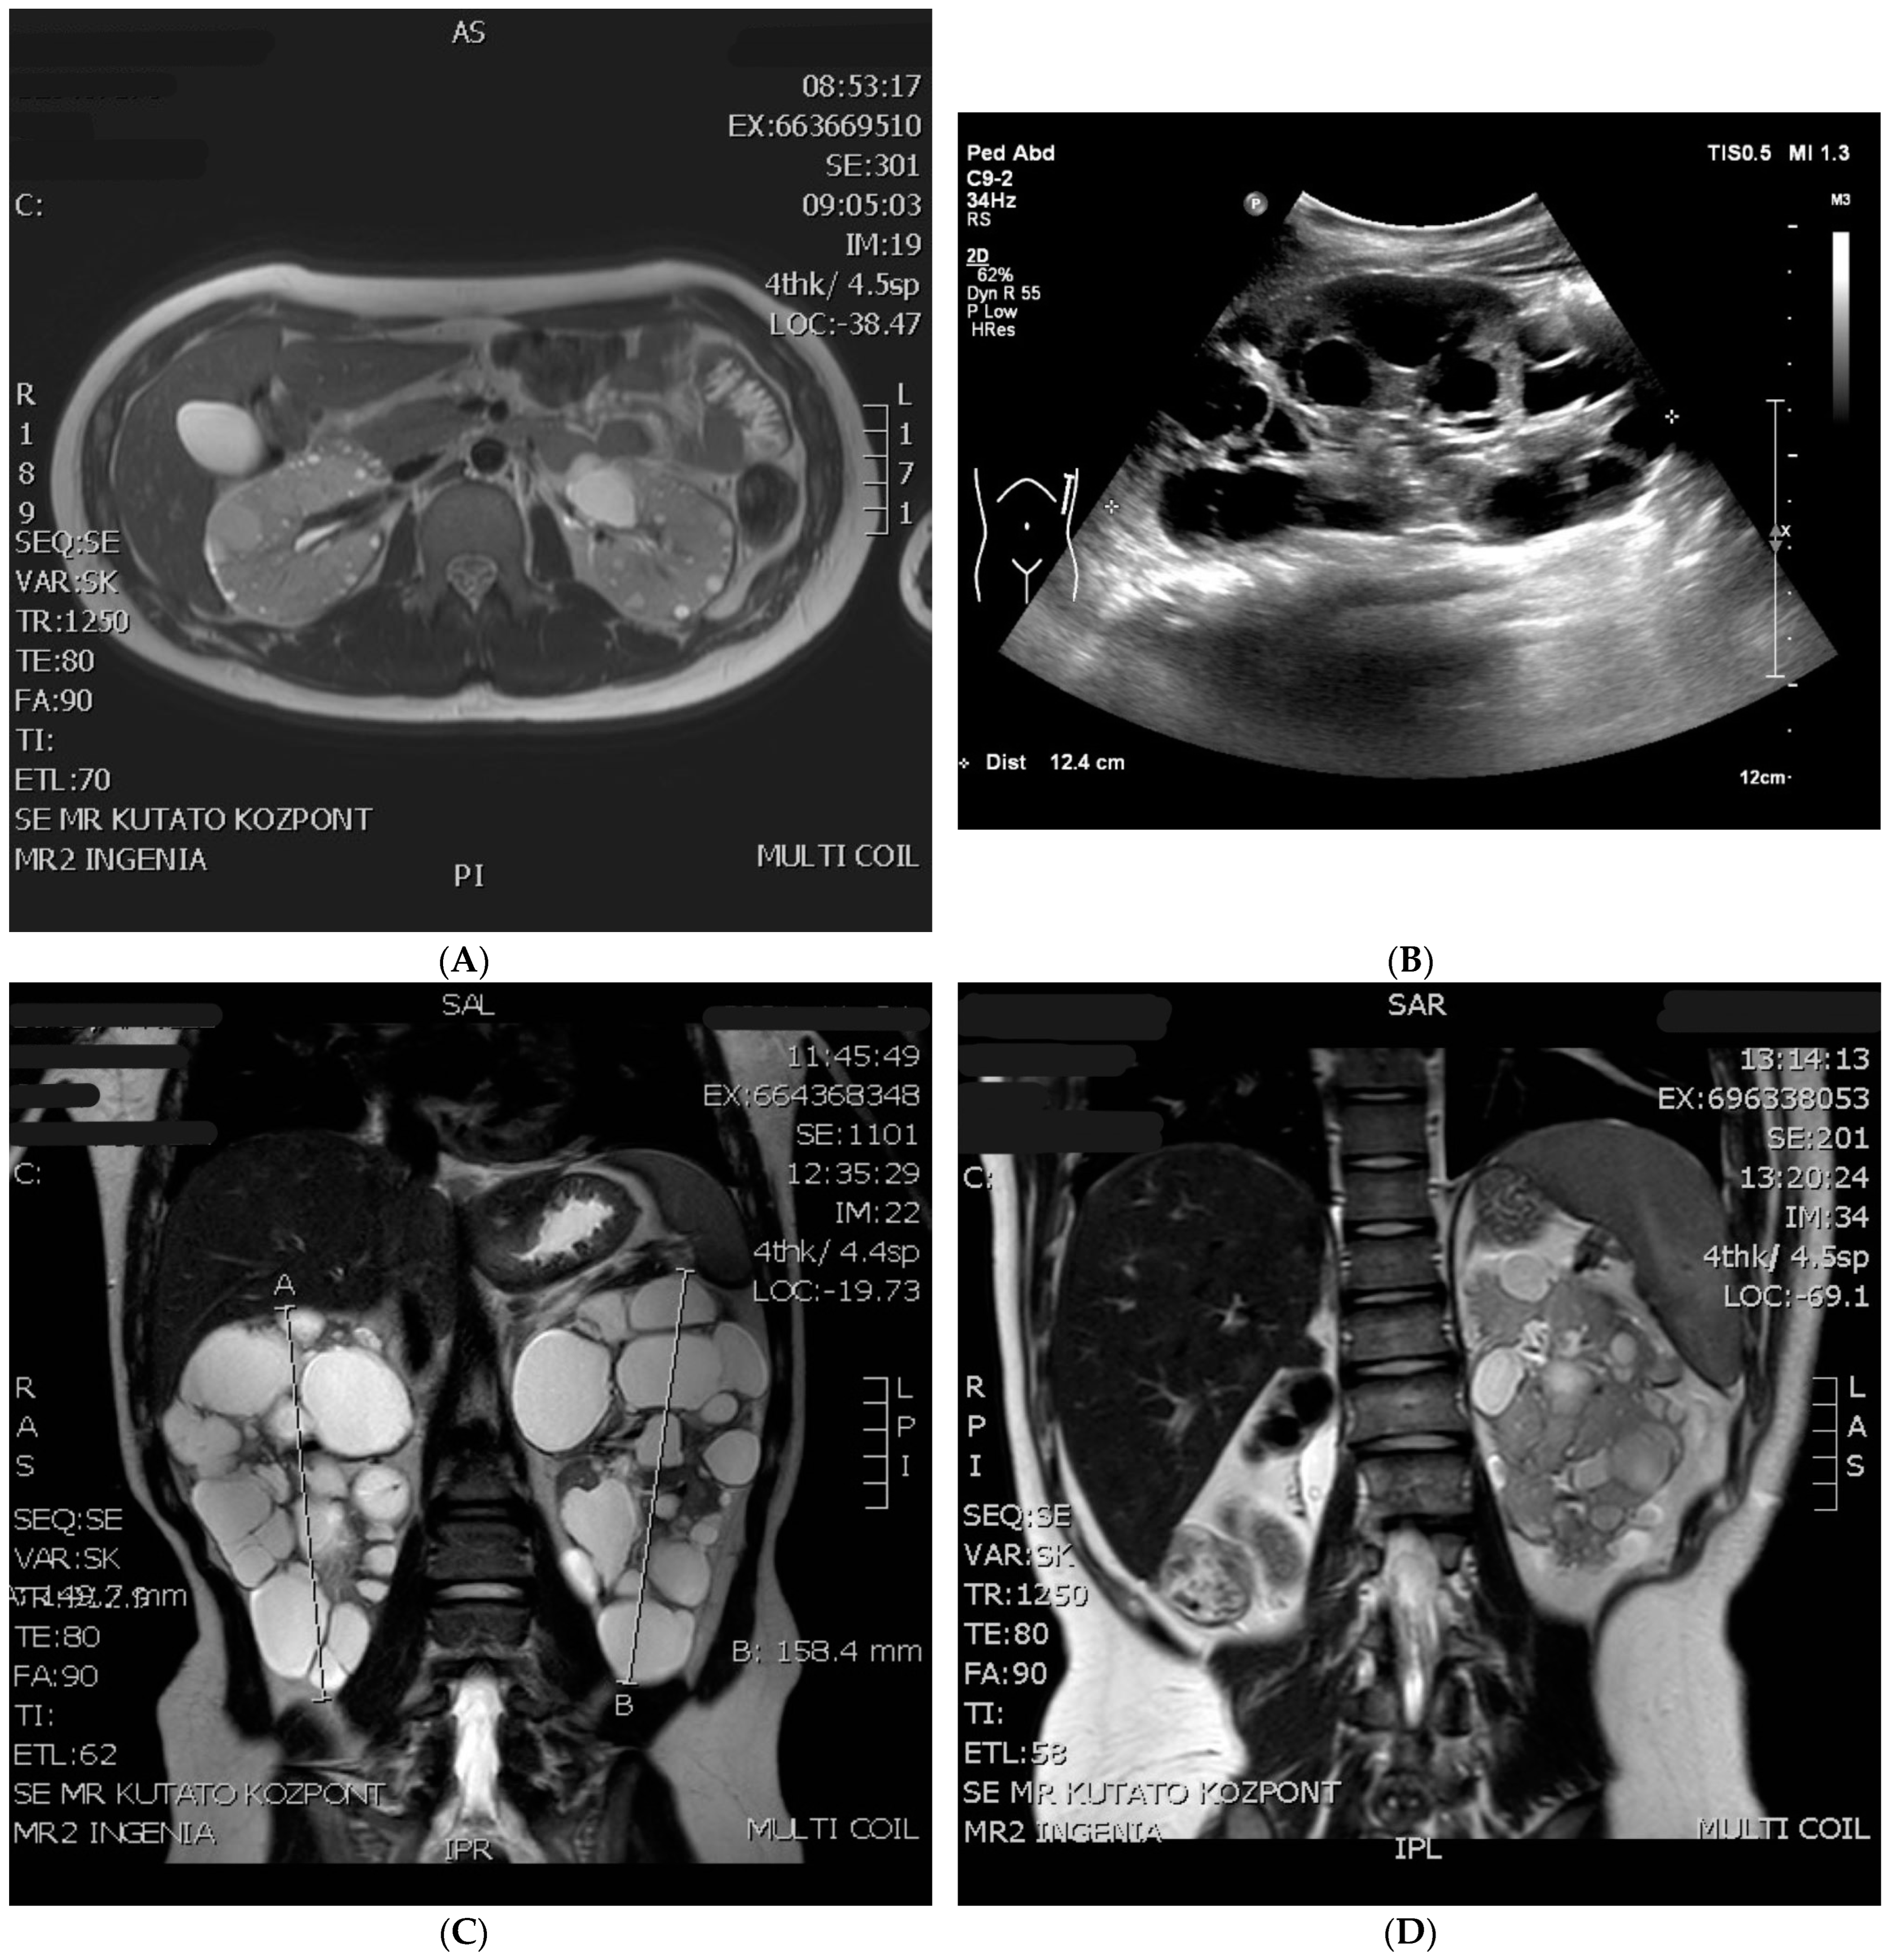

2. Case Reports